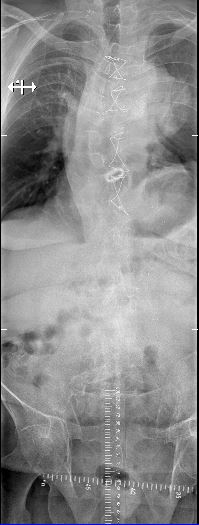

Omdat ik de foto’s ook voor mezelf wil hebben, zetten ze voor € 10,- de foto’s op dvd. Best wel aardig dat het zo kan. Ik heb 2 foto’s gekopieerd zodat deze in dit bericht geplaatst kunnen worden. Nu zie je pas goed dat de scoliose boven in de kolom (zie achteraanzicht foto links) best mee valt maar de Kyphoscoliose onder in de wervel (foto zijaanzicht foto rechts) wel heel groot is. Op de foto rechts zie je ook goed de kunst aortaklep (de witte schijf die op een muntje lijkt) en op de linkerfoto zie je de draadjes die om het borstbeen zitten.

Dr. Willems bekijkt de foto’s en komt tot de volgende conclusies:

1. De wervels komen gelukkig nog niet tegen elkaar aan.

2. De pijn zit steeds in de lange rugspieren omdat ze constant op spanning (overbelast) staan. De spieren regelmatig los     proberen te maken door de fysiotherapeut en door de chiropractie zal al voor een paar dagen verlichting kunnen zorgen.Die ervaring heb ik al. Ga regelmatig naar Chiropractie Daams te Stein. Ook hij weet heel wat van orthopedie en pijnverlichting.

3. Regelmatig therapie en vooral in warm water bewegen is goed voor de spieren. Ook dat doe ik al.

4. Tegen de pijn in mijn rug en rechterbeen kunnen ze me pijnstillers geven.

5. Om pijn proberen te voorkomen kan er een korset worden aangemeten. Dit ter ondersteuning van mijn spieren.Moet het niet de hele dag dragen anders worden de spieren weer te slap.

6. Een laatste optie maar is een rugoperatie. Maar dit is echt als niets anders meer helpt. De risico’s zijn heel groot. De bochel wordt dan weliswaar kleiner en de pijn minder. Het heeft geen zin om verdere details van een operatie te bespreken omdat dit voorlopig niet zal gebeuren.

We besluiten samen om een korset aan te laten meten. Ik krijg daar meteen een verwijzing voor.